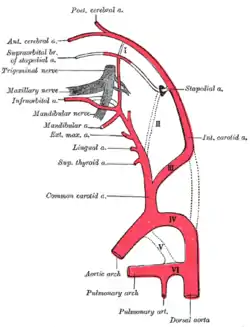

Diagram showing the origins of the main branches of the carotid arteries.

Diagram showing the origins of the main branches of the carotid arteries. Bloodvessels of the eyelids, front view.